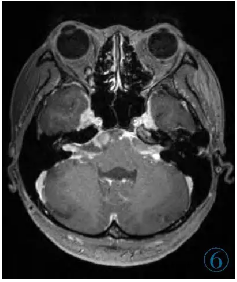

,予抗结核联合糖皮质激素

图6 1月后复查MR示软脑膜弥漫性增厚、强化情况较前进展,脑室较前扩大,结节较前增大。